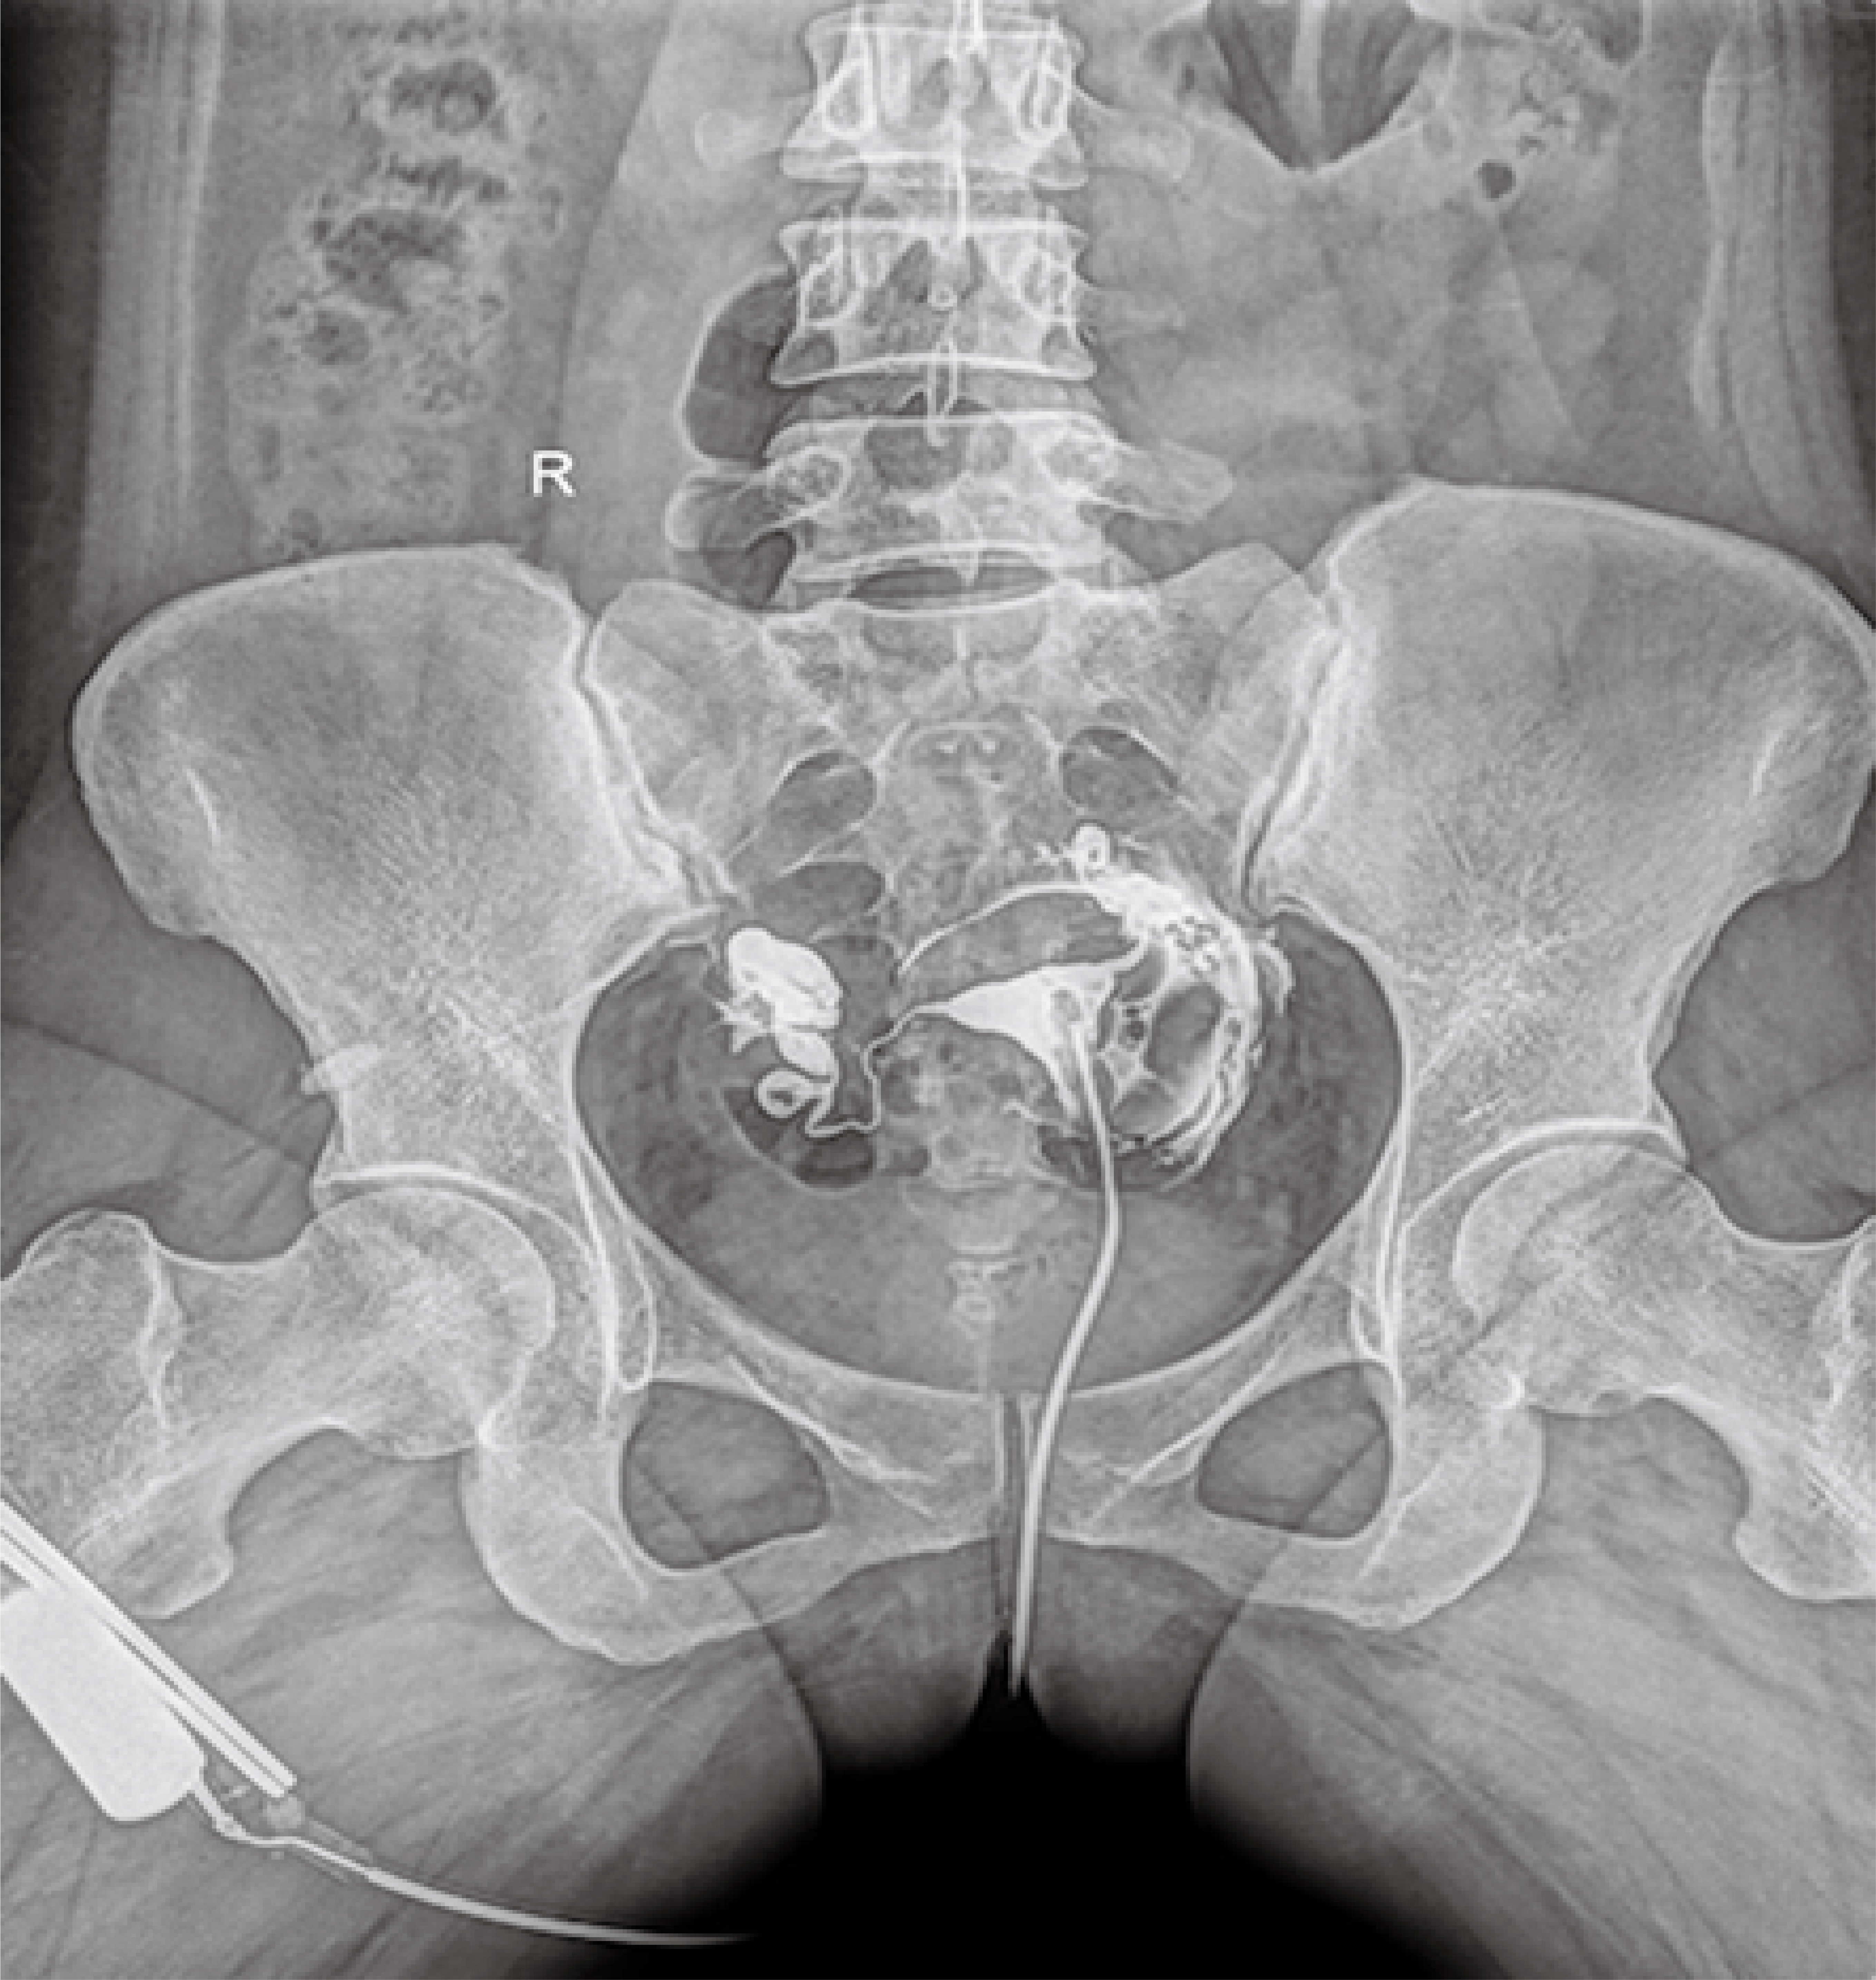

● 17*17英寸的超高清像素動(dòng)態(tài)平板探測(cè)器,更大的視野范圍,無(wú)需移動(dòng)即可觀察整個(gè)動(dòng)態(tài)過(guò)程,避免拖尾、噪聲對(duì)圖像的影響;

● 高效動(dòng)態(tài)平板技術(shù),圖像不會(huì)有幾何畸變,提供高分辨率和精確的圖像,為醫(yī)生臨床診斷提供精準(zhǔn)依據(jù);

● 最高幀速可達(dá)30幀/秒,動(dòng)態(tài)采集清晰流暢,避免漏診、誤診情況的發(fā)生;

● 在可視過(guò)程或回放過(guò)程中,如發(fā)現(xiàn)疑似病灶,可進(jìn)行毫秒級(jí)高清點(diǎn)片,隨時(shí)抓取單幀圖像,精準(zhǔn)捕抓病灶。